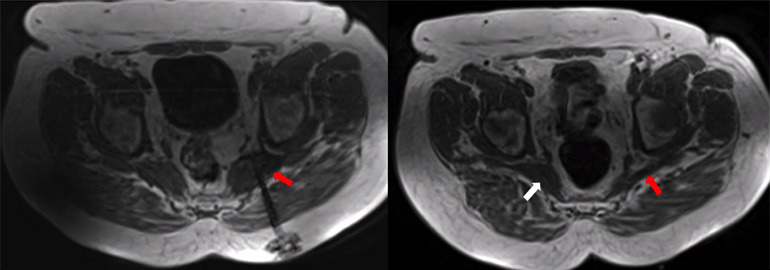

The lymphatic system transports tissue fluid, fats, and immune cells. Disorders can cause lymph leakage or drainage problems, leading to conditions such as chylothorax, lymphatic fistulas, or persistent fluid collections. Lymphangiography is a minimally invasive imaging technique in which contrast agent is injected into lymph vessels (usually in the foot or groin) to visualize the lymphatic system and detect leaks using MRI. It also enables treatment: leaking vessels can be sealed and abnormal connections corrected, often avoiding surgery. Our group uses lymphangiography for both precise diagnosis and minimally invasive therapy, allowing targeted treatment even of very small lymph vessels. Below you can see a the lymphatic system in the pelvis of a patient and the leakage causing lymph to exit (Fig. 6).